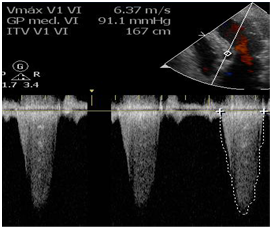

Transthoracic echocardiogram at admittance

After admittance, the patient underwent a transthoracic echocardiogram where we observed a left ventricle outflow tract gradient of 91 mmHg, as well as apical dyskinesia (Figure 2 & 3).

Figure 2 Left ventricle outflow gradient of 91 mmHg (Taken at admittance).